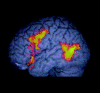

Studies of spoken and written language suggest that the perception of sentences engages the left anterior and posterior temporal cortex and the left inferior frontal gyrus to a greater extent than non-sententially structured material, such as word lists. This study sought to determine whether the same is true when the language is gestural and perceived visually. Regional neural activity was measured using functional MRI while Deaf and hearing native signers of British Sign Language (BSL) detected semantic anomalies in well-formed BSL sentences and when they detected nonsense signs in lists of unconnected BSL signs. Processing BSL sentences, when contrasted with signed lists, was reliably associated with greater activation in the posterior portions of the left middle and superior temporal gyri and in the left inferior frontal cortex, but not in the anterior temporal cortex, which was activated to a similar extent whether lists or sentences were processed. Further support for the specificity of these areas for processing the linguistic-rather than visuospatial-features of signed sentences came from a contrast of hearing native signers and hearing sign-naïve participants. Hearing signers recruited the left posterior temporal and inferior frontal regions during BSL sentence processing to a greater extent than hearing non-signers. These data suggest that these left perisylvian regions are differentially associated with sentence processing, whatever the modality of the linguistic input.